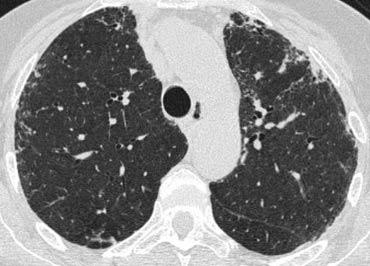

Bên trái là bệnh nhân nữ 47 tuổi với triệu chứng ho khan, khó thở nhẹ và xét nghiệm máu bình thường.

Bệnh nhân được chụp X-quang ngực và điều trị kháng sinh.

Phim kiểm tra được chụp lại do bệnh nhân không cải thiện.

Phim X-quang ngực đầu tiên cho thấy đông đặc hai bên ở thùy dưới (mũi tên), ban đầu được diễn giải là nhiễm trùng.

Sau hai tuần điều trị kháng sinh, không có cải thiện.

Chẩn đoán phân biệt lúc này bao gồm u ác tính (ung thư phế quản phế nang hoặc u lympho), viêm phổi tăng bạch cầu ái toan, viêm phổi tổ chức hóa, bệnh Wegener hoặc một thể không điển hình của sarcoidosis.

Tiếp tục với hình ảnh HRCT.

Hãy cuộn qua các hình ảnh bên trái.

Có nhiều vùng đông đặc.

Các dấu hiệu kèm theo bao gồm hạch to rốn phổi và trung thất.

Chẩn đoán phân biệt trên hình ảnh CT về cơ bản giống như trên X-quang ngực.

Kết quả mô bệnh học xác nhận sarcoidosis phế nang.

Chỉ có một gợi ý duy nhất cho chẩn đoán, đó là sự hiện diện của các nốt nhỏ có thể nhận thấy ở hình 3, nhưng rất khó quan sát.

Trường hợp này minh họa rõ ràng rằng sarcoidosis thực sự là “kẻ bắt chước vĩ đại”.

Do đó, sarcoidosis cần được đưa vào danh sách chẩn đoán phân biệt của chúng ta!